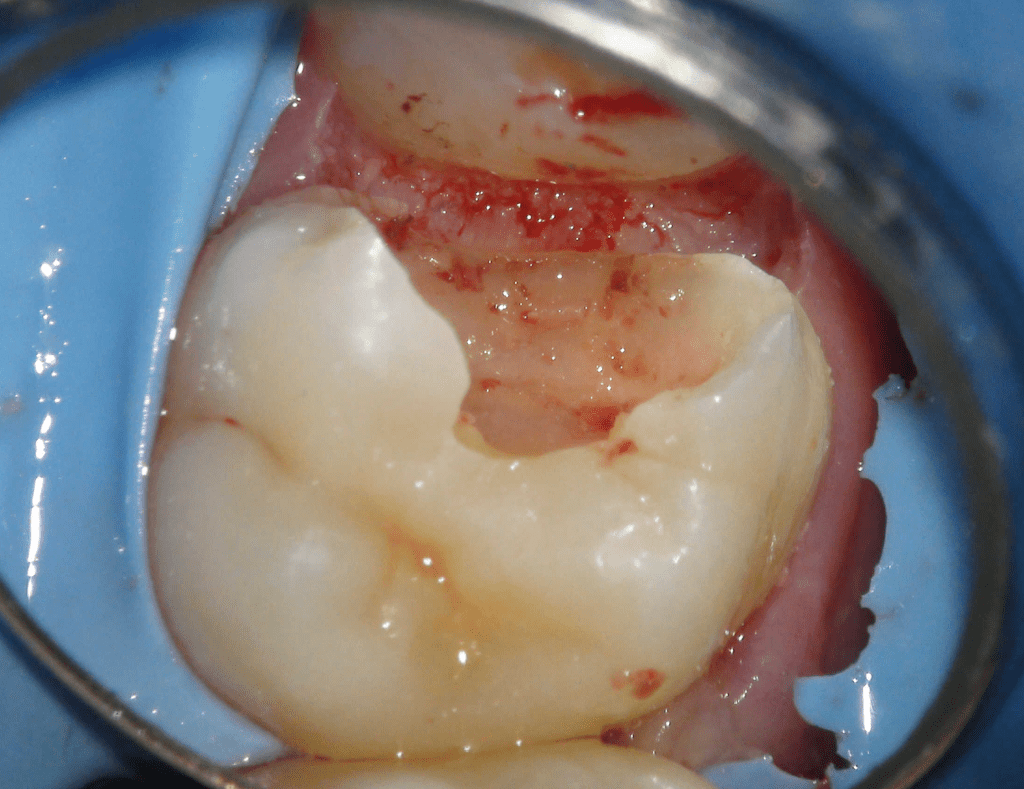

Pulpotomía biodentine + reco preendio